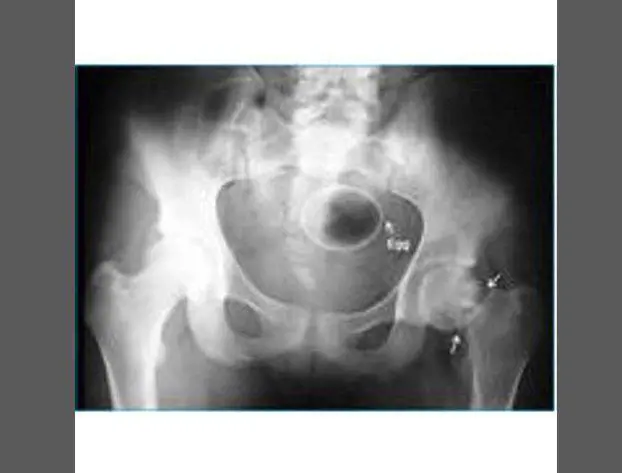

Oggetti bizzarri che hanno trovato la loro strada all'interno del corpo umano, e documentati grazie alle pazze radiografie raccolte dal dottor Frank Gaillard. Quest’ultimo ha fondato Radiopaedia.org, un sito collaborativo che raccoglie casi radiologici e articoli medici a tema.